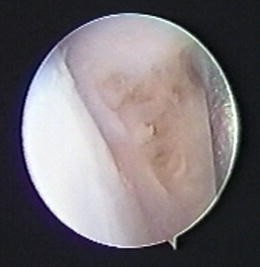

Fig. 3